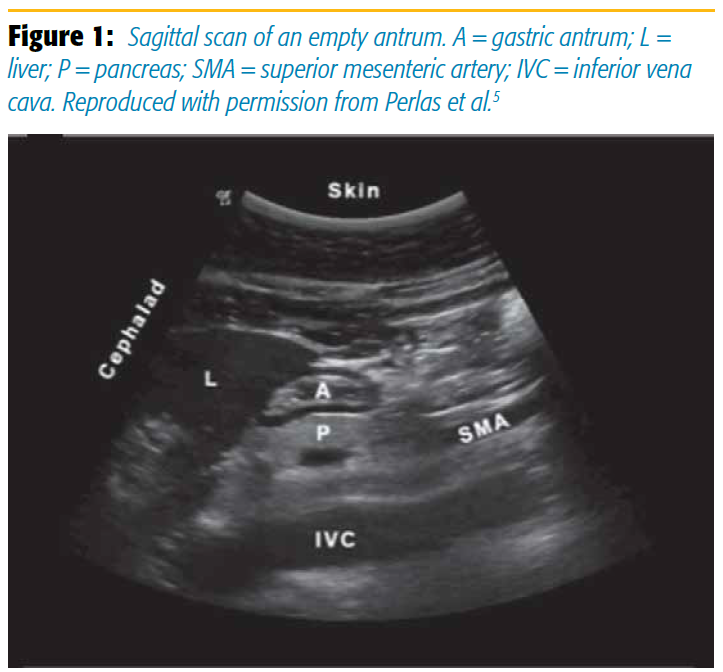

The goal of point-of-care gastric ultrasound is to evaluate the gastric antrum, as the content and size of the antrum correlate with the content and volume of the entire organ. Scanning with a curvilinear probe in a sagittal plane over the epigastrum, the antrum appears round or oval and is found between the liver anteriorly and the pancreas posteriorly. The aorta or inferior vena cava is located posterior to the pancreas. The superior mesenteric artery can sometimes also be seen (Figure 1). The antrum has a characteristic five-layered wall. These five layers alternate between hyper- and hypoechoic. Although the antrum itself is located at an average depth of 4–5 cm, an initial scanning depth of 12–15 cm is recommended to properly identify all regional anatomical landmarks.